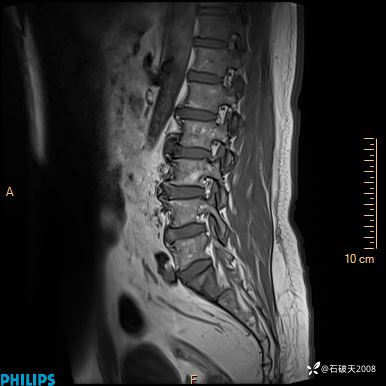

2023年3月份MRI影像

T2矢状位压脂